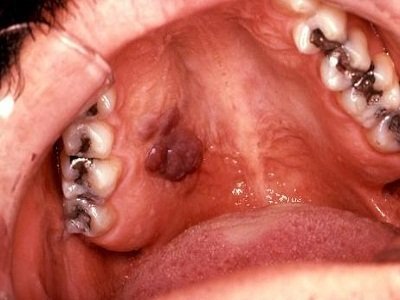

Sùi mào gà là một trong số 8 căn bệnh lây nhiễm qua đường tình dục, mức độ nguy hại của nó đối với sức khỏe con người không thể coi nhẹ. Sùi mào gà là bệnh lây truyền qua đường tình dục do nhiễm HPV, biểu hiện bằng các sẩn sùi mềm ở sinh dục ngoài có khi ở hậu môn hoặc vùng da khác như ở miệng. Tác nhân gây bệnh là HPV (human papiloma virus), thuộc loại papova virus có DNA. Chủ yếu lây truyền qua đường tình dục, còn có thể lây truyền qua tiếp xúc. Trẻ sơ sinh có thể bị lây bệnh từ người mẹ mắc bệnh trong lúc sinh đẻ.

Mụn cóc sinh dục (HPV). Mụn cóc sinh dục là một trong những loại bệnh phổ biến nhất lây truyền qua đường tình dục. Như tên cho thấy, mụn cóc sinh dục nằm tại vùng sinh dục. Có thể mụn nhỏ như da gà, có màu hoặc có kích thước lớn giống như mào gà( sùi mào gà).